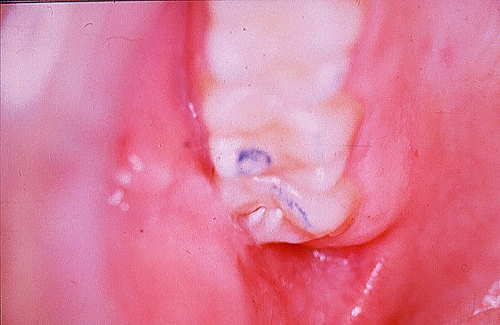

En ciertas áreas del saber humano, el lenguaje confuso o criptográfico Muchas son las técnicas elaboradas para lograr un desgaste selectivo, y numerosos autores han expuesto en su momento variadas formas de lograr una función oclusal fisiológica mediante el ajuste de la misma. Han pasado años desde entonces y, sin embargo, aún hoy, un altísimo porcentaje de profesionales “navega” por el mar de la confusión oclusal, dada la diversidad de conceptos y escuelas, sin lograr arribar a costa alguna donde poder anclar un conocimiento sólido sobre cómo tratar la oclusión Ya se esté realizando una simple obturación, endodoncia, incrustación, radectomía u ortodoncia, la lógica pocas veces, en la mayoría de los casos, vincula un tratamiento con otro, siendo el resultado final el mismo caos inicial; enmascarado por mucho tratamiento profesional. El ajuste oclusal es un medio inicial de proveer al sistema enfermo de: Dicha técnica, que puede ser terapéutica en sí misma; consta de dos etapas, a saber: 1) Ajuste Oclusal por Adición Mediante el estudio de la guía anterior, encargada de efectuar las Disclusiones durante las excursiones mandibulares, podremos observar si ésta es funcional o no. • Marcas de carácter continuo, si en ese recorrido se produce la Disclusión de los sectores posteriores y todo marcha correctamente. FIG 1-2 Si por el contrario observamos: • Marcas de carácter discontinuo, significa que dicha Disclusión se está efectuando por medio de una pieza dentaria posterior a la guía anterior. FIG 3-4-5 (FIGS. 3, 4 Y 5). En la figura 6 las flechas indican, en un caso clínico de análisis oclusal, la presencia de marcas discontinuas que indican Interferencias en Propulsiva. FIG 6-7 Y por último, si existieran: • Abrasiones de las áreas discluyentes en las áreas de diagnóstico de la guía anterior, deberemos aportar material a dicha zona para no permitir el choque lateral de las piezas posteriores (Ajuste Oclusal por Adición) En las imágenes 11 y 12 podemos observar la adición de composite en la punta de un canino derecho, previa la observación de la Faceta Parafuncional remarcada durante el análisis oclusal en el articulador. (FIGS. 8 A 12). 2) Ajuste oclusal por Sustracción o Desgaste Habiendo cumplido ya con la verificación de la funcionalidad de la Guía Anterior, comenzamos los desgastes en céntrica, a fin de lograr un único arco de cierre, guiado eficazmente por la Guía Anterior; es decir: la coincidencia entre Oclusión Habitual y Oclusión en Relación Céntrica. En este caso, intentar gastar dichos puntos, de ser posible sólo en las cúspides de corte o no fundamentales: • Crestas Triangulares Internas, Cúspides Vestíbulares Superiores • y un poco de las Crestas Triangulares Internas, Cúspides (FIGS. 13 A 16). Si la deflección es hacia el lado opuesto, se invierten los desgastes. En las migraciones hacia adelante, las únicas razones posibles están en los puntos estabilizadores (FIG. 17); es decir: -Vertientes Distales de los Rebordes Marginales, Triangulares (FIG 17) (FIG 18 A-B-C-D) Obsérvese cómo, en una boca prácticamente entera, comienzan a “desmoronarse” prismas adamantinos (FIG. 19), como consecuencia de un punto prematuro de contacto, ubicado en la posición de un estabilizador, que provoca la discrepancia horizontal postero-anterior causante de dicho efecto (FIG. 20). FIG 19-20 Dicho punto, será necesario ajustarlo antes de cualquier tratamiento en la zona ¿Cuáles serían las consecuencias si esos incisivos fueran implantados tal como es frecuente observar en múltiples congresos y cursos de implantología, donde el tema de la oclusión no es más que un cuadro polifacético y anecdótico? 14 15 16 17 Todo producto del adelantamiento mandibular Realizados ya los desgastes en céntrica, obteniendo de esta manera un único arco de cierre, es decir, oclusión en relación céntrica, debemos realizar el ajuste de las excéntricas, apoyando la acción de la guía anterior, para lo FIG 22 a. De un lado a otro de un mismo maxilar, la imagen es especular, o sea invertida. b. En hemimaxilares cruzados, la imagen es idéntica. Allí donde existan colisiones entre cúspides, se deberá crear un surco para que dicha cúspide antagonista migre a su través, tanto en el lado de no trabajo, como en el de trabajo y en el de propulsión. FIG 23 Es importante conservar esta parte del surco, ya que si no existieran, los contactos entre cúspides serían en superficie y no puntiformes (fig. 24). FIG 24 1. Obtener un único arco de cierre con coincidencia entre oclusión habitual y relación céntrica. 2. El cierre mandibular debe ser recibido sólo por la tabla premolar-molar. 3. Durante las excursiones funcionales es la guía anterior la que debe sufrir las fuerzas laterales. 4. De cumplirse estas dos premisas debemos obtener libertad de desplazamiento (no confundir con libertad en céntrica) a las piezas posteriores mediante la creación de surcos disclusivos. Examinadas ya las posibles migraciones mandibulares y los desgastes o aposiciones necesarios para poder ocluir en céntrica, es fundamental recordar que, previamente a todo tipo de ajuste, se ha hecho necesario ubicar a la mandíbula en relación céntrica. Para ello debemos utilizar el propio funcionalismo muscular 22 FIG 25 Y esto no significa otra cosa que: piezas dentarias estables en todos los planos del espacio, ATM centrada en la cavidad glenoidea, periodontos sin tensión, músculos en la dimensión de elongación adecuada para un fisiologismo Paz absoluta en la intimidad del Sistema Estomatognático. Y así, como corolario final, es posible establecer una regla de oro similar en importancia a la conocida formula: Forma = Función Ésta es: FIG 26 FUNDAMENTOS NEUROFISIOLÓGICOS DEL REGISTRO DE OCLUSIÓN EN RELACIÓN CÉNTRICA ( ORC) MEDIANTE EL USO DE LAMINILLAS DE LONG CUADRO

Usamos como medio las laminillas de long (fig. 25), estimulando con ellas las fibras anteriores o verticales del músculo temporal, disociando cualquier estímulo precedente del sector posterior, responsable de los Engramas pertinentes a la deflexión y, por lo tanto, al estimular un elevador, por inervación recíproca, relajar un depresor.